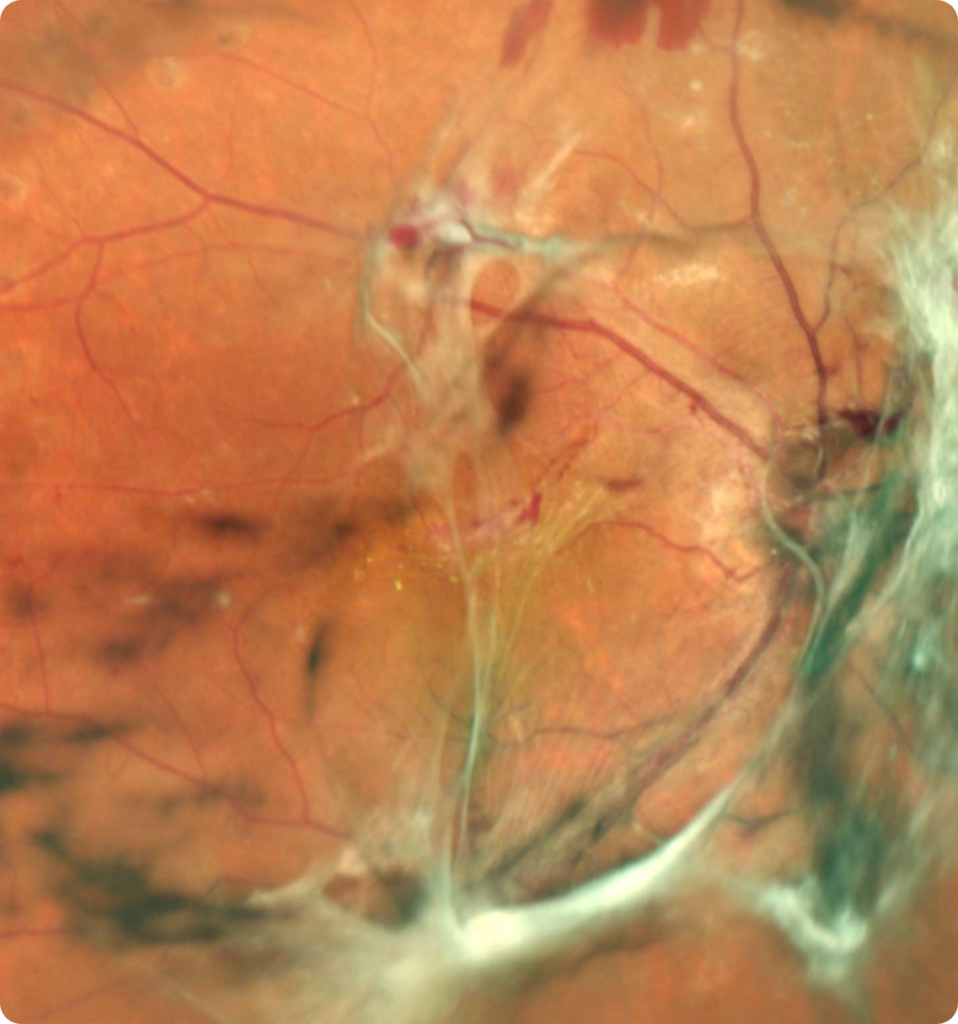

Si el daño a la retina continúa, aparecen en la retina vasos sanguíneos nuevos (conocidos como neovasos), cuya intención es llevar más oxígeno y nutrientes a la retina, pero que en realidad sólo sirven para causar las complicaciones de la enfermedad que pueden poner en riesgo la visión de manera permanente. Cuando aparecen estos vasos anormales, la retinopatía diabética se conoce como proliferativa.

Estos neovasos pueden romperse, causando una hemorragia vítrea, es decir, que la sustancia transparente que rellena el ojo llamada humor vítreo se manche de sangre, causando disminución súbita de la visión.

Estos mismos neovasos pueden causar un desprendimiento de retina, o si crecen en la parte anterior del ojo, pueden causar glaucoma neovascular.

Si se detecta una hemorragia vítrea o un desprendimiento de retina, puede ser necesaria una cirugía llamada vitrectomía, cuya finalidad es extraer el humor vítreo y la hemorragia, y/o reparar el daño a la retina.